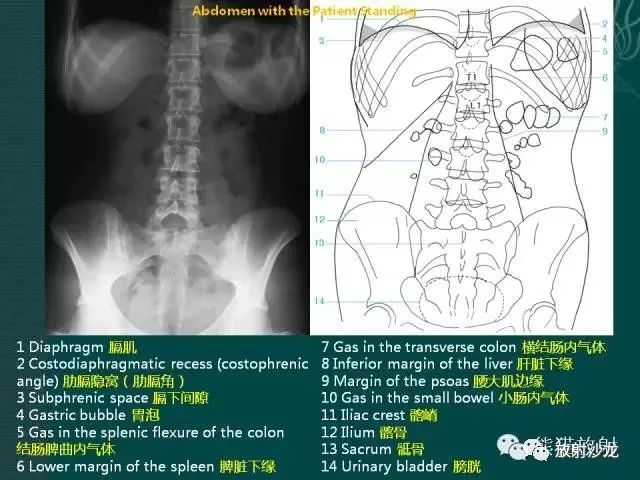

腹部平片解剖

腹部平片正常表现

腹部脏器有实质器官和空腔脏器之分,其正常腹平片表现不同。

● 腹平片上实质器官的正常表现:

实质器官:肝、胰、脾和肾等是中等密度,但借助于器官周围或邻近的脂肪组织和相邻充气肠胃的对比,于腹平片上,可显示器官的轮廓、大小、形状及位置。

正位片在部分病人可显示肝下缘,肝下缘与肝外缘相交形成肝角,一般呈锐角。

脾上极与左膈影融合,下极较圆钝。而肾沿腰大肌上部排列。

胰腺于平片上不易显示。子宫偶尔显影,位于膀胱上缘上方呈扁圆形软组织影。

● 空腔脏器在腹平片上的主要表现:

空腔器官:膀胱的脏壁为中、胆囊和肠胃道等密度,依腔内容物不同而x线表现不同。

胃、十二指肠球部及结肠内可含气体,于腹平片上可显示其内腔。小肠除婴幼儿可有积气外,一般充满食糜及消化液,与肠壁同属中等密度,因缺乏对比而不能显示。

如胃内有较多固态食物,结肠或直肠内有较多粪便,由于它们周围有气体衬托,故可显出软组织密度斑片或团块影。

结肠分布于腹部四周。膀胱和胆囊周围有较多脂肪,也可显示部分边缘。